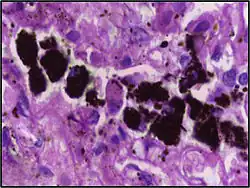

Comparison of pigmented pulmonary macrophages

| Disease | Macrophage name | Macrophage pigment appearance (HE stain) | Usual macrophage location | Associated medical history | Image | Image comment |

|---|---|---|---|---|---|---|

| Chronic pulmonary congestion | Siderophages | Brown-golden and refractile.[5] | Alveoli[6] |

|

Siderophage (black arrow), and interstitium with edema, hemosiderin deposition (black arrow) and collagenous thickening, indicating heart failure. |